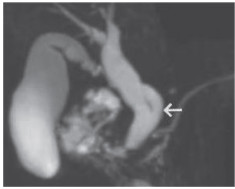

1 临床资料患者,女,66岁,因腹痛于外院诊断“胆总管末端结石”1月余后收入我院,欲行内镜逆行胰胆管造影术(endoscopic retrograde cholangiopancreatography,ERCP)取石治疗。术前实验室检查提示白细胞计数3.44×109/L,总胆红素(total bilirubin,TBIL)13.8 μmol/L,直接胆红素(direct bilirubin,DBIL)3.4 μmol/L。全腹增强CT检查提示胆总管略宽。超声检查提示胆总管内径约0.95 cm,胆总管上段管腔内条带状回声(图 1)。因不排除有胆总管小结石自行排出的可能,且为明确是否需行ERCP,进一步行内镜超声检查。内镜超声检查提示肝外胆管内未见强回声,故患者未行ERCP取石治疗。因患者自觉无明显不适,且无手术治疗指征,符合出院标准,医嘱建议其出院后3~6个月门诊复查超声、腹部CT或磁共振胰胆管成像(magnetic resonance cholangiopancreatography,MRCP),病情变化随诊。

| 箭头所示为胆总管内条带状回声. 图 1 首次超声检查图像 |

胆囊管解剖变异的诊断主要借助影像学检查,MRCP是目前胆道解剖学检查中侵入性最小、最可靠的检查方法[8],能全面地显示胰胆管的解剖结构及连接关系,可诊断包括LICD在内的胆管解剖变异[9],有文献[10]报道MRCP诊断胆管解剖变异的准确率高达96.9%。但MRCP对胆管周围组织的定性诊断较差,且易受伪影影响,目前仍不能作为胆道系统疾病的常规检查项目。超声检查是诊断胆道疾病的首选方法,但目前对于LICD的超声诊断报道较为罕见,这可能与未扩张的胆囊管在超声检查中显示困难及超声医生对胆囊管解剖变异认识不足有关。本例患者在既往超声检查中,由于初诊超声医生对LICD认识不足,将相互伴行的胆囊管和肝总管误认为胆总管上段,将胆囊管和肝总管二者相重叠的管壁回声误认为胆总管上段腔内的条带状回声(图 1),而复查超声时发现第一肝门处2条胆管回声,右侧的胆管向上与胆囊相连接,为冗长扩张的胆囊管(图 2A),左侧胆管与肝内的左右肝管相连接,为扩张的肝总管,最终二者汇合成胆总管进入胰头(图 2B),胆囊管在肝外胆管下段汇入,因此,超声诊断为LICD。但超声检查目前很难确定胆囊管汇入点的位置,还需借助MRCP进一步明确。本例LICD患者的3D-MRCP图像可清晰显示胆囊管汇入点位于胆总管的左侧壁(图 3),属LICD的低位螺旋汇入。